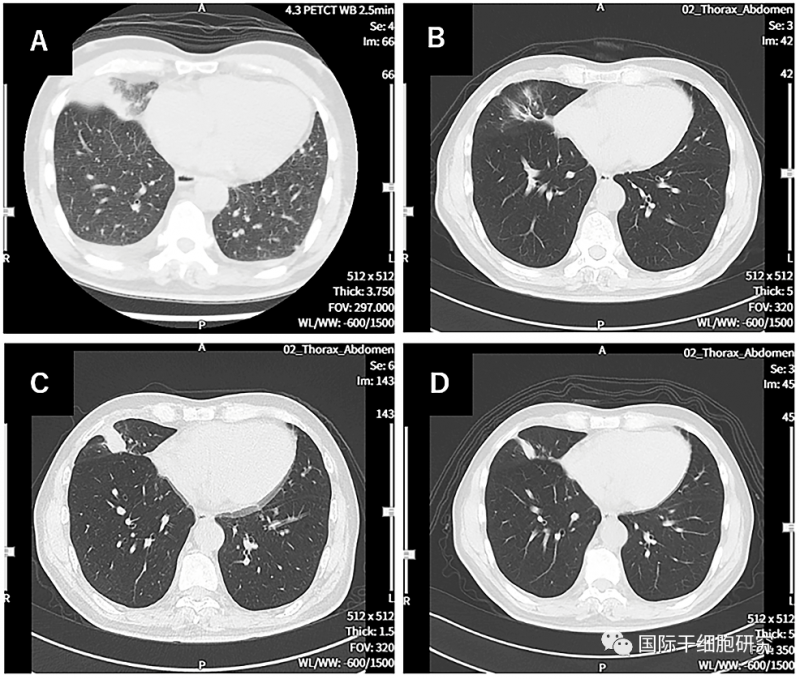

图2 胸部CT图像对比

图片A(诊断时的CT图像):示原发性右下肺癌,伴左右胸腔积液。

图片B(治疗第114天的CT图像):示原发病灶几乎消失。

图片C(治疗第213天的CT图像):示原发病变存在一定程度的复发。

图片D(治疗第338天的CT图像):示原发性、复发性病变缩小。